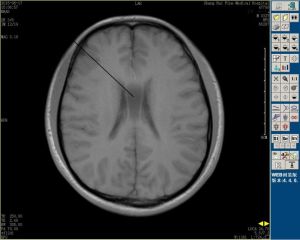

英文名Centrumsemiovale,為大腦半球中心呈半卵圓形的白質區,主要有胼胝體的輻射纖維以及經內囊的投射纖維等組成。在半球上部橫切面上是半卵圓形,故有此名。